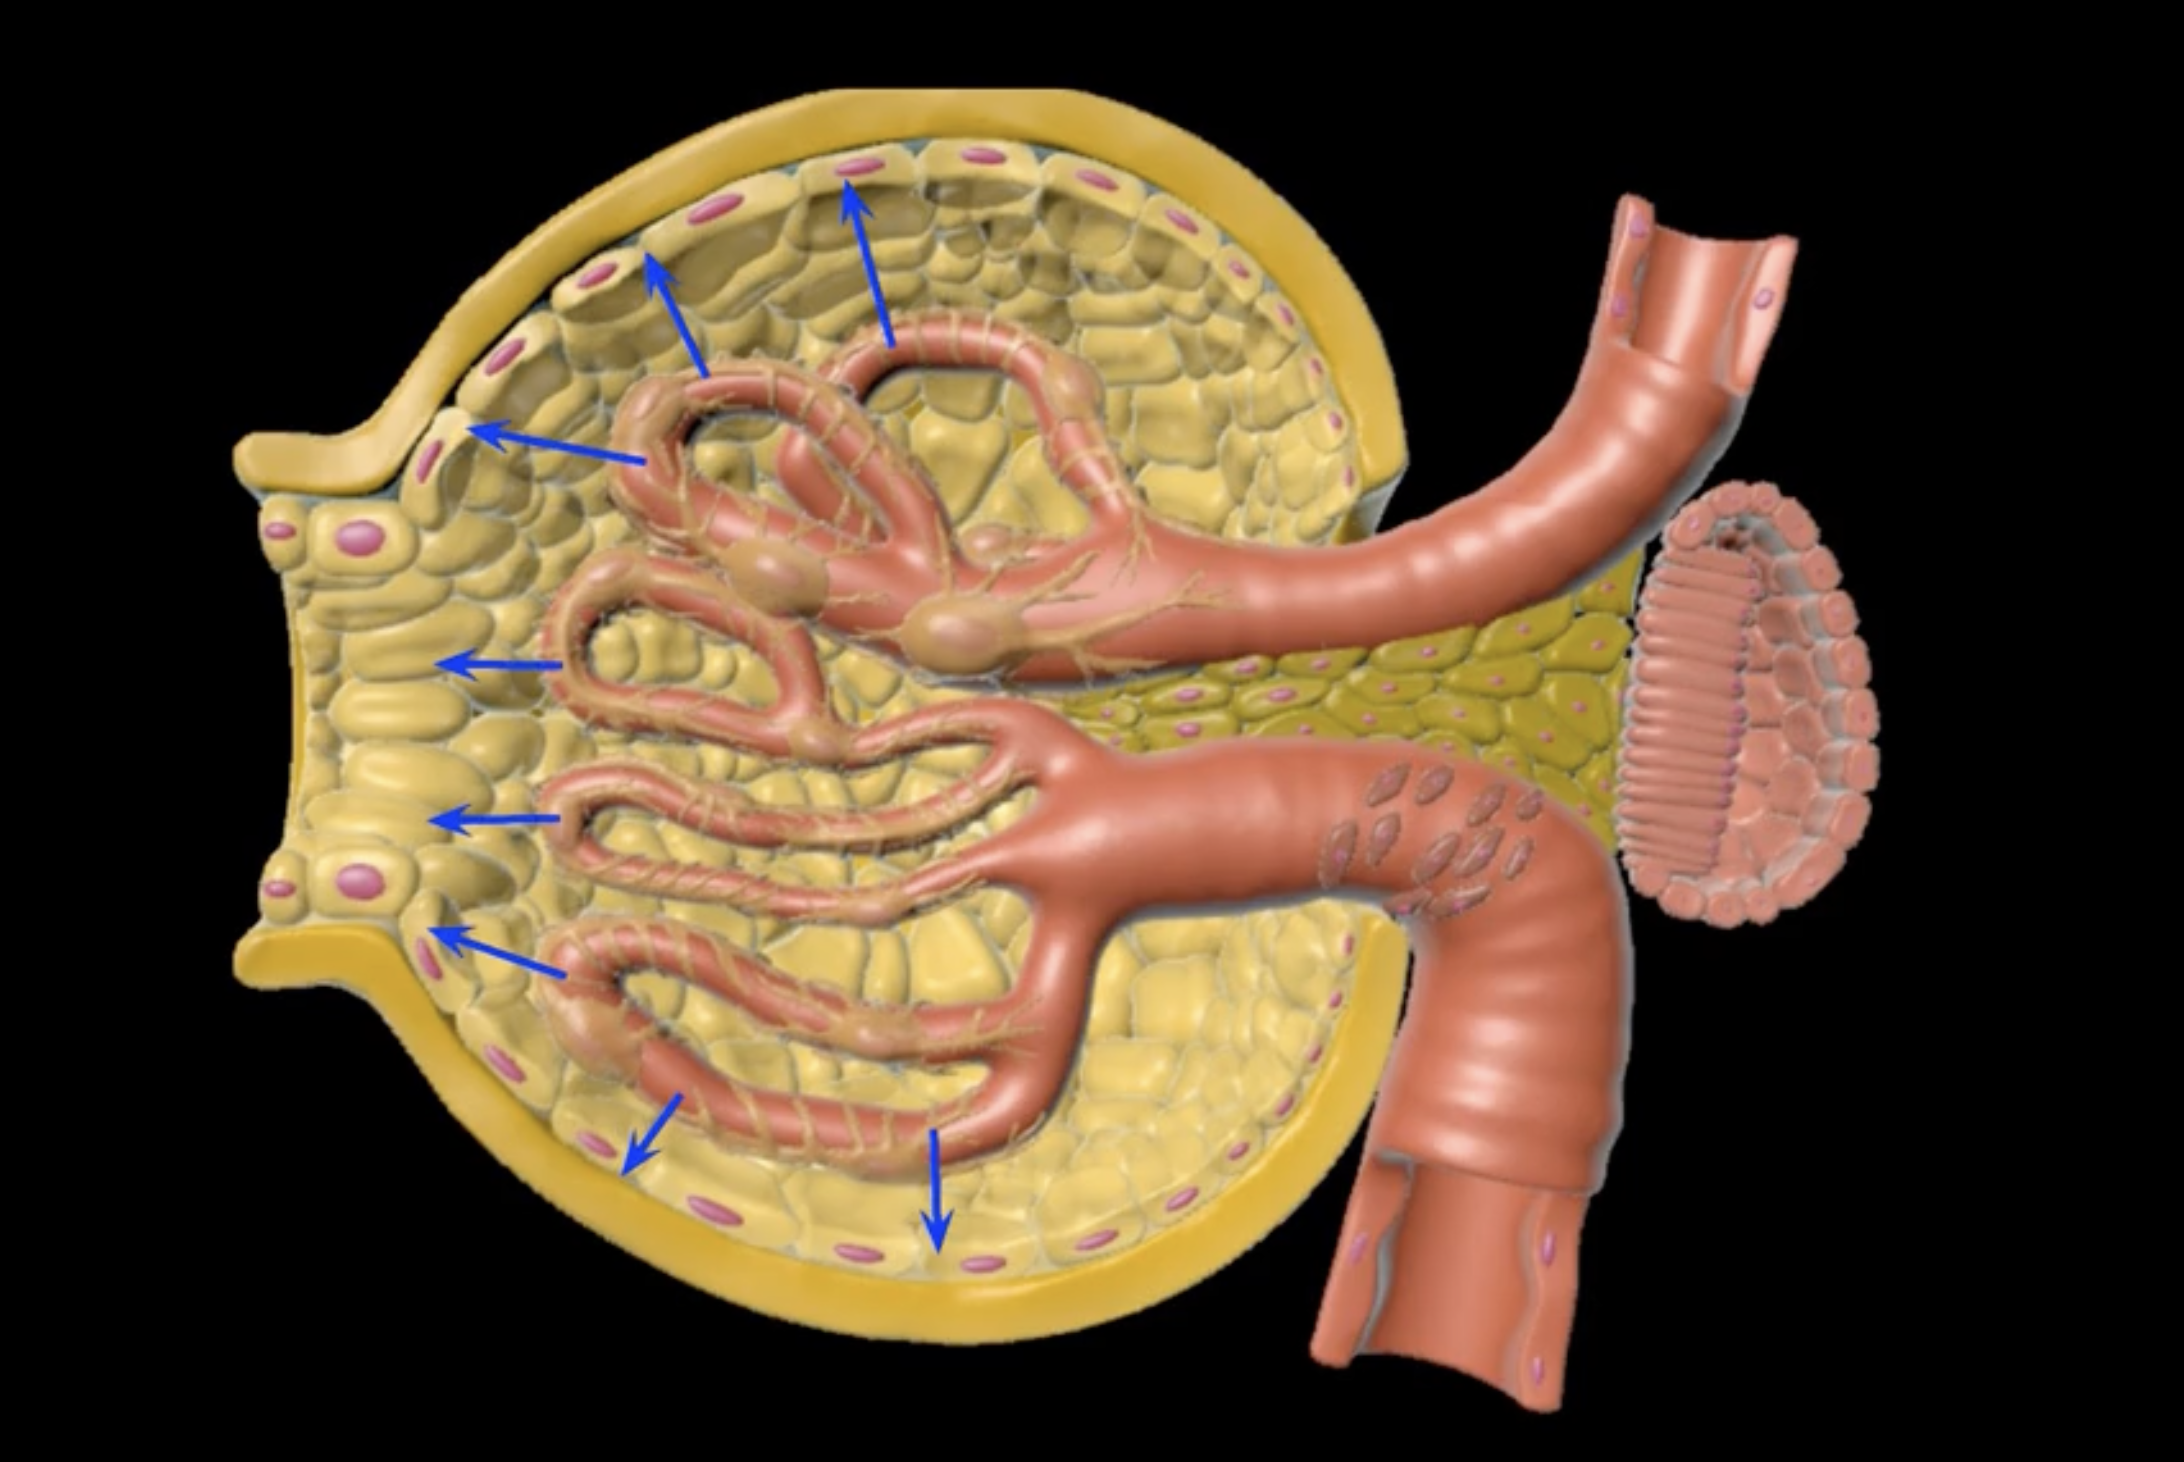

Podocytes

nephron

type of cell

Bowman’s capsule

Glomerular filtration involves pressured movement of fluid and solutes from the blood into ___ (blue arrows)

capillaries

orange

green

endothelium

filtration membrane is composed of ____ (yellow)

visceral layer of Bowman’s capsule

purple

basement membrane

blue

afferent arteriole

visceral layer

orange cells

foot processes

filtration slits/slit diaphrams

yellow

capsular space

outlined in blue

blue space